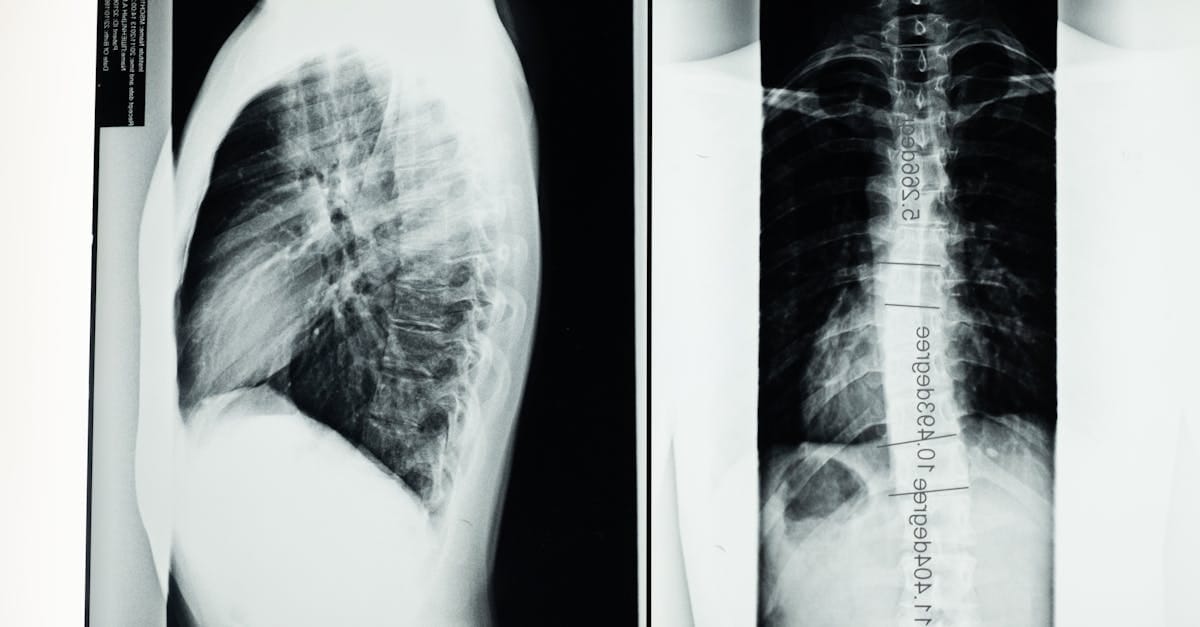

- Diagnosis: Medical imaging (MRI, X-rays).

Spinal stenosis is a condition characterized by the narrowing of the spinal canal, the space that houses the spinal cord and nerve roots. This narrowing can lead to pressure on the nerve structures, causing varied symptoms such as pain, numbness, or difficulties walking. Spinal stenosis is often caused by degenerative factors, including arthritis, and primarily affects older individuals. As the spine ages, modifications to its structures can occur, leading to a decrease in the caliber of the spinal canal.

Spinal stenosis is a common condition that primarily results from the narrowing of the spinal canal, causing pressure on the spinal cord and spinal nerves. This compression can lead to various symptoms, including pain, numbness, and difficulties walking. Effective treatments, such as spinal decompression, are essential to relieve the signs and improve the quality of life of patients suffering from this pathology.